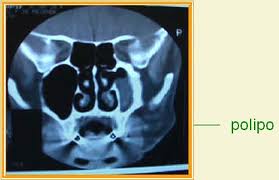

Pólipos nasais

Os pólipos nasais são formações carnudas da membrana mucosa nasal.

As pessoas que sofrem de alergias que afectam o nariz (rinite alérgica) têm tendência para ter pólipos nasais. Os pólipos também podem formar-se durante infecções e desaparecer uma vez que esta diminua de intensidade. Os pólipos costumam crescer nas áreas onde a membrana mucosa se inflamou devido a uma acumulação de líquido, como na zona que rodeia as aberturas dos seios dentro da cavidade nasal. Enquanto se está a desenvolver, o pólipo assemelha-se a uma lágrima e quando está maduro parece-se com uma uva pelada sem grainha.